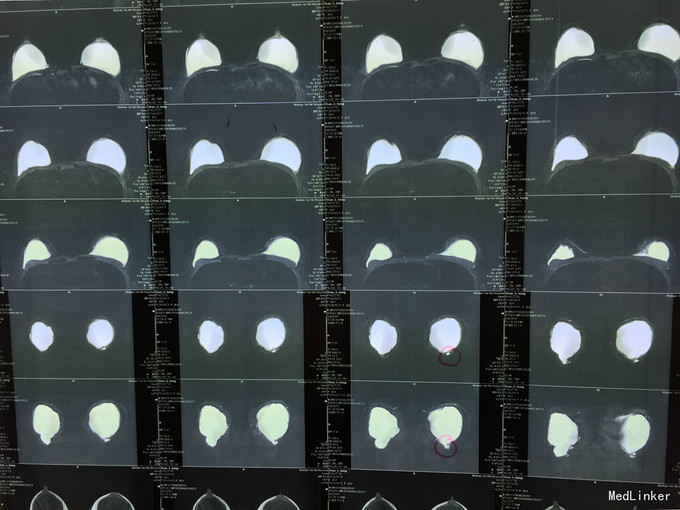

39岁患者,十余年前因乳房发育不良行“奥美定注射隆胸术”,术后恢复情况可。十余年来未出现并发症。近两周来患者出现左胸部疼痛,遂来我院就诊,门诊诊断“双侧乳房注射隆胸术后”。

查体:生命体征平稳,神志清楚,查体配合。心肺腹体格检查未见明显异常。专科情况:双侧乳房大小较一致,左侧稍高于右侧,表面皮肤颜色正常,无破溃处出现。乳房触之较软,左侧乳房有压痛。 辅查:胸部磁共振影像资料

诊断:双侧乳房注射隆胸术后 治疗:手术治疗。沿乳晕边缘做切口,逐渐分离乳房皮下组织。至注射物包膜层后,小心切开包膜,挤出其中的注射物后,用剪刀清扫周围包膜。留置引流管后美容缝合切口。